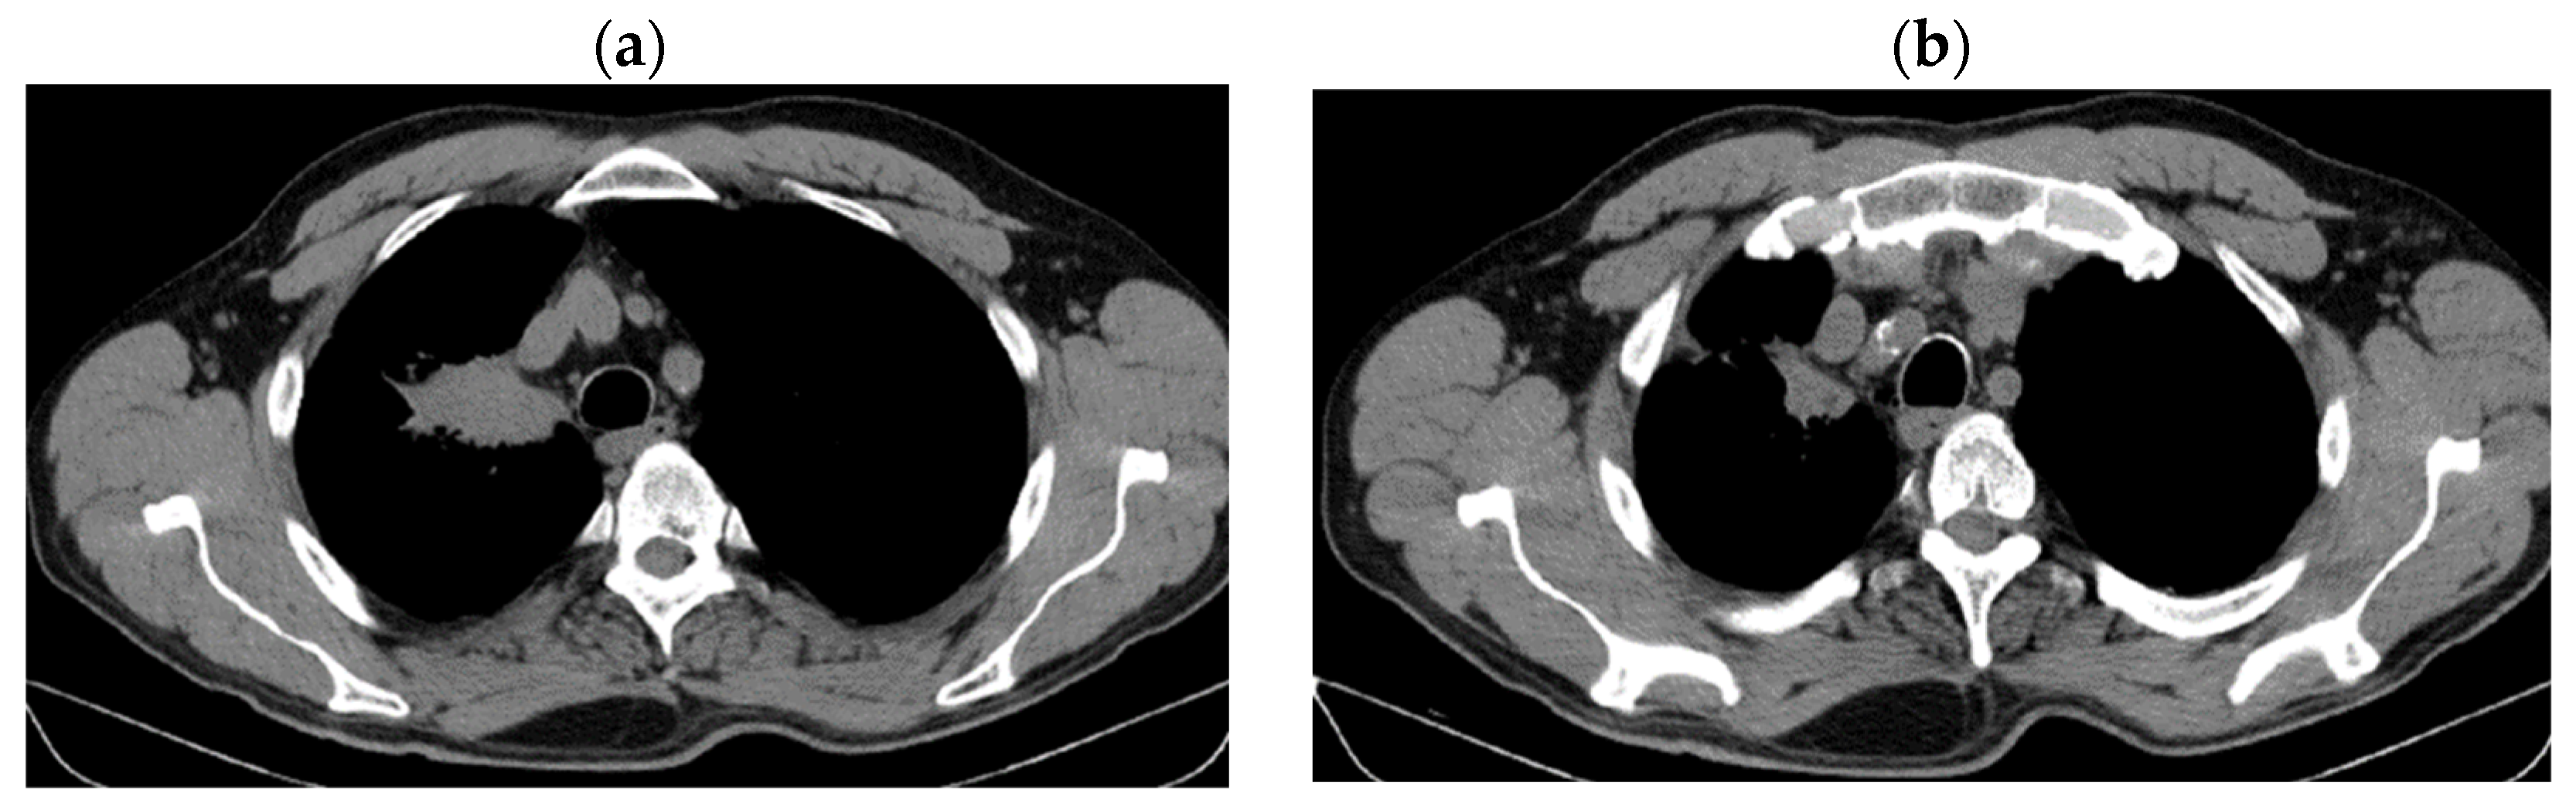

2. Case Presentation

2.1. Systemic Third-Line Therapy (4xDocetaxel) Was Initiated 04–07/2020

2.2. Monitoring 2022: Oncological Commission 1910/16.08.2022

2.3. Oncological Committee 07/25/2023 Recommended